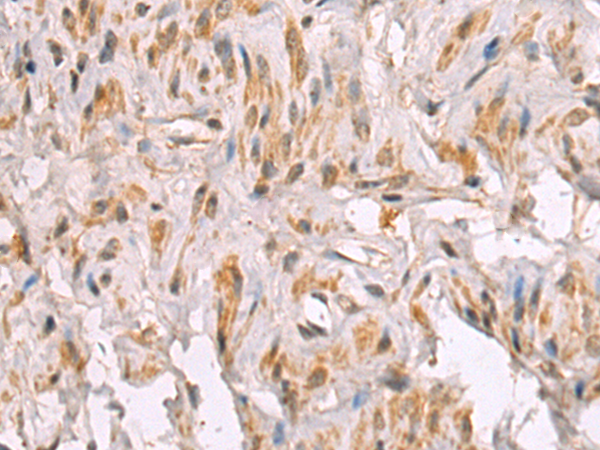

分类: 科研抗体货号: P06464别名: LRAP; L-RAP应用: IHC反应种属: Human